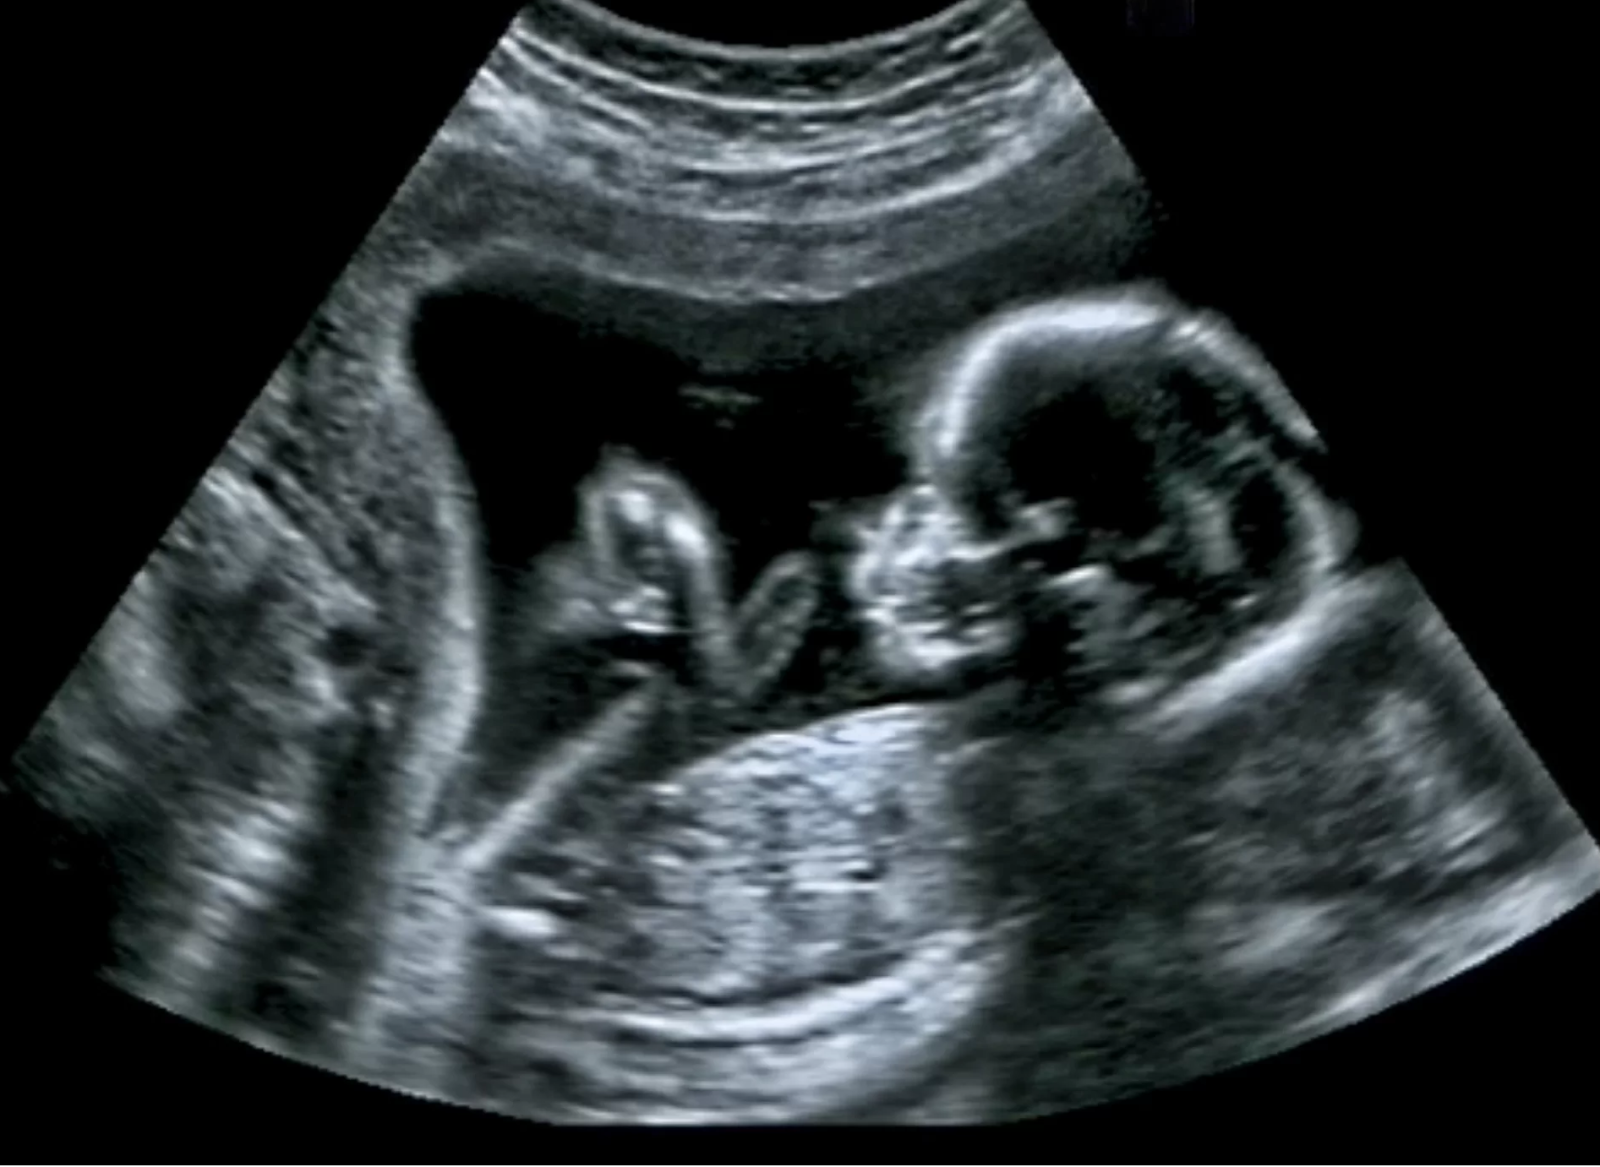

22/12/2018ช่วงเวลาที่น่าตื่นเต้นที่สุดระหว่างตั้งครรภ์ จะเป็นช่วงไหนไปไม่ได้นอกจากตอนที่แม่รู้สึกถึงการดิ้นของลูกเป็นครั้งแรก แต่คุณรู้หรือไม่ว่าจริง ๆ แล้วเวลาที่แม่รู้สึกว่าลูกกำลังเตะท้อง นั่นอาจสื่ออะไรได้มากกว่าที่คุณคิด นักวิจัยพบว่า ทารกสามารถสร้างเครือข่ายสมองขั้นพื้นฐานเพื่อให้สามารถเข้าใจว่าส่วนใดของร่างกายกำลังเคลื่อนไหวและมีสัมผัสเป็นอย่างไร เครือข่ายสมองนี้ถูกสร้างภายในไม่กี่วันหลังจากพวกเขาเกิด นักวิจัยตั้งข้อสังเกตว่าการเคลื่อนไหวแบบเดิมหลาย ๆ ครั้ง จะส่งผลกระทบต่อสมองในแบบเดิม หากเป็นเช่นนั้นการเคลื่อนไหวในขณะที่ทารกอยู่ในครรภ์นี้อาจเป็นการเตรียมตัว เพื่อให้โครงสร้างประสาทที่ซับซ้อนได้ทำการสร้างตัวรับสัมผัสต่าง ๆ และตอบสนองต่อการกระตุ้นทันทีเมื่อออกมาสู่โลกภายนอก นักวิจัยเสนอว่าการตอบสนองพื้นฐานนี้จะเป็นทักษะที่สามารถใช้ได้ทันทีเหมือนการดูดนมของทารก Kimberley Whitehead…